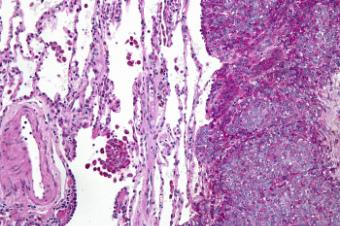

К группе неэпителиальных новообразований относятся опухоли, в структуру которых входят недифференцированные веретенообразные и округлые клетки. Часто в состав миксоидной стромы, которая заполняет пространство между клетками, входят клетки с разной дифференцировкой, характерные для поперечно исчерченных мышечных тканей. Иногда клетки опухоли состоят из миофибриллов с поперечной исчерченностью или из хрящей.

Опухоль покрыта плоским эпителием в несколько слоев. Для нижней трети влагалища характерно развитие злокачественных меланом и невусов. Во время диагностики патологию дифференцируют от папилломы, фиброэпителиальными полипами.